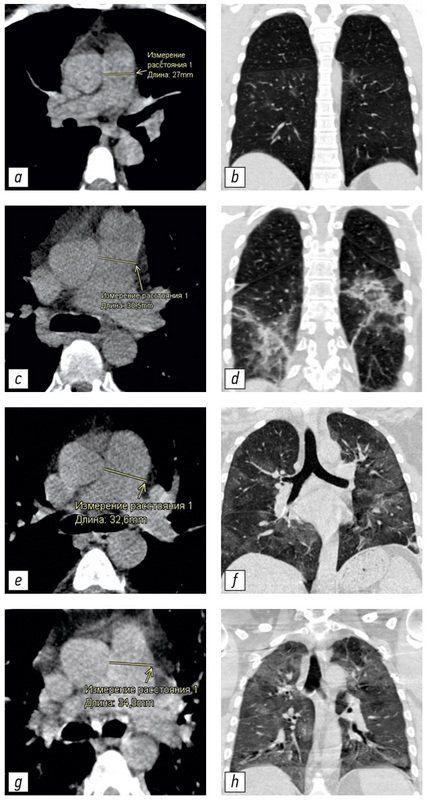

Changing of pulmonary artery diameter in accordance with severity of COVID-19 (assessment based on non-contrast computer tomography)

BACKGROUND: Computed tomography is the method of choice for assessing the volume of lung damage in viral pneumonia, including those associated with COVID-19. In addition, computed tomography can determine the main vessels size of the thorax. This allowed us to analyze the relationship between the severity of COVID-19 and the changes in the diameters of the pulmonary artery (PA) and ascending aorta (Ao). Dilation of the PA is a sign of pulmonary hypertension. The study of these patterns may be of clinical significance in determining the treatment tactics and prognosis of the course of COVID-19 disease.

AIM: To evaluate the relationship between PA diameter and the severity of the COVID-19 course in patients of different ages.

MATERIALS AND METHODS: This study is a single-centered, cross-section, continuous, uncontrolled study performed on a group of patients (n=511, 267 men, median 59 years, IQR 49.0–65.0, ages 31–84 years) who were treated in a temporary hospital to treat patient with COVID-19. During hospitalization all patients were examined by CT scan of the chest. All studies were carried out using a mobile CT scan system Airo TruCT (Stryker, USA). The degree of damage to the lung tissue was assessed using the CT volume scale 1–4. Measurement of the LA and Ao diameters was carried out using standard instruments of the radiologist’s CT workstation perpendicular to the long axis of the vessel.

RESULTS: The following statistically significant regularities were obtained: the detection of a dilated pulmonary artery (PA) and an increased PA/Ao ratio correlated to an increase in the degree of lung damage in COVID-19 (Kruskal-Wallis test, K-W p <0.001; median test, MT p <0.001), the diameter of the ascending aorta (Ao) significantly increases with the patient’s age (K-W p <0.001; MT p <0.001). An insignificant correlation between an increase in the diameter of the pulmonary artery (PA) and the patient’s age (K-W p=0.094; MT p=0.311) and an insignificant correlation between detection of a change in aortic (Ao) diameter and the degree of lung damage (K-W p=0.061; MT p=0.165) were shown. In groups with a severe course of the disease and a large volume of lung lesions (CT-3 and CT-4), a significantly greater number of patients with signs of pulmonary hypertension (detection of the dilated pulmonary artery: 29 mm and more) was shown for all age groups.

CONCLUSION: The study showed that PA dilatation and increased PA/Ao diameter ratio were significantly associated with increased pulmonary lesion volume in COVID-19 in all age groups.